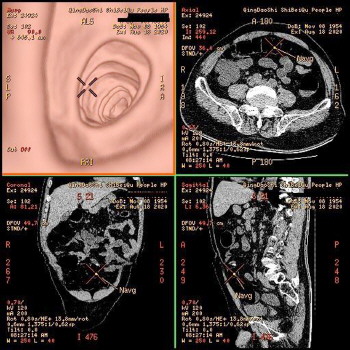

市北区人民医院放射科潜心施展螺旋CT检查功能,于年内推出仿真内窥镜检查项目。螺旋CT仿真内窥镜,是充分利用三维后处理技术。肺部疾病患者,仅需配合几秒钟屏气CT扫描;肠道疾病患者,提前做好肠道清洁准备,检查时经肛门注入空气对比,仅需几秒钟CT扫描即可。经过计算机三维重建处理,不用侵入体内就能十分清晰地观察气管、结肠等空腔器官的内表面,准确发现肺癌、结肠癌肿块及息肉等病变,基本无创伤和无副作用,是十分安全有效的检查手段。为基础疾病多的老年患者,存在各种风险不能做结肠镜检查的患者,以及对内窥镜创伤性检查望而却步的患者,提供了新的临床检查选择。目前,该院已为诸多不明原因肠梗阻、结肠息肉、结肠肿瘤性疾病、肺不张及肺癌等患者,进行了效果显著的检查及诊断。(贝仁奕)